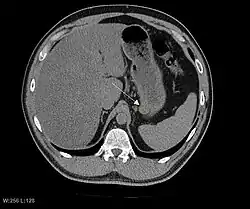

КТ-скан без контрастного усиления, демонстрирующий небольшую субсерозную ГИСО из задней стенки желудка (стрелка). Случайная находка.

Так как ГИСО происходят из мышечного слоя (который располагается глубже слизистого и подслизистого слоёв), небольшие ГИСО чаще визуализируются как подслизистое или внутристеночное объёмное образование. При исследовании желудочно-кишечного тракта с барием обычно выявляются ровные контуры образования, формирующие прямой или тупой угол со стенкой, что наблюдается и при любых других интрамуральных процессах. Поверхность слизистой интактна, за исключением случаев изъязвления, которые присутствуют при 50 % ГИСО. При КТ с контрастным усилением, небольшие ГИСО обычно визуализируются как интрамуральные образования с ровными, чёткими контурами и гомогенным контрастированием.